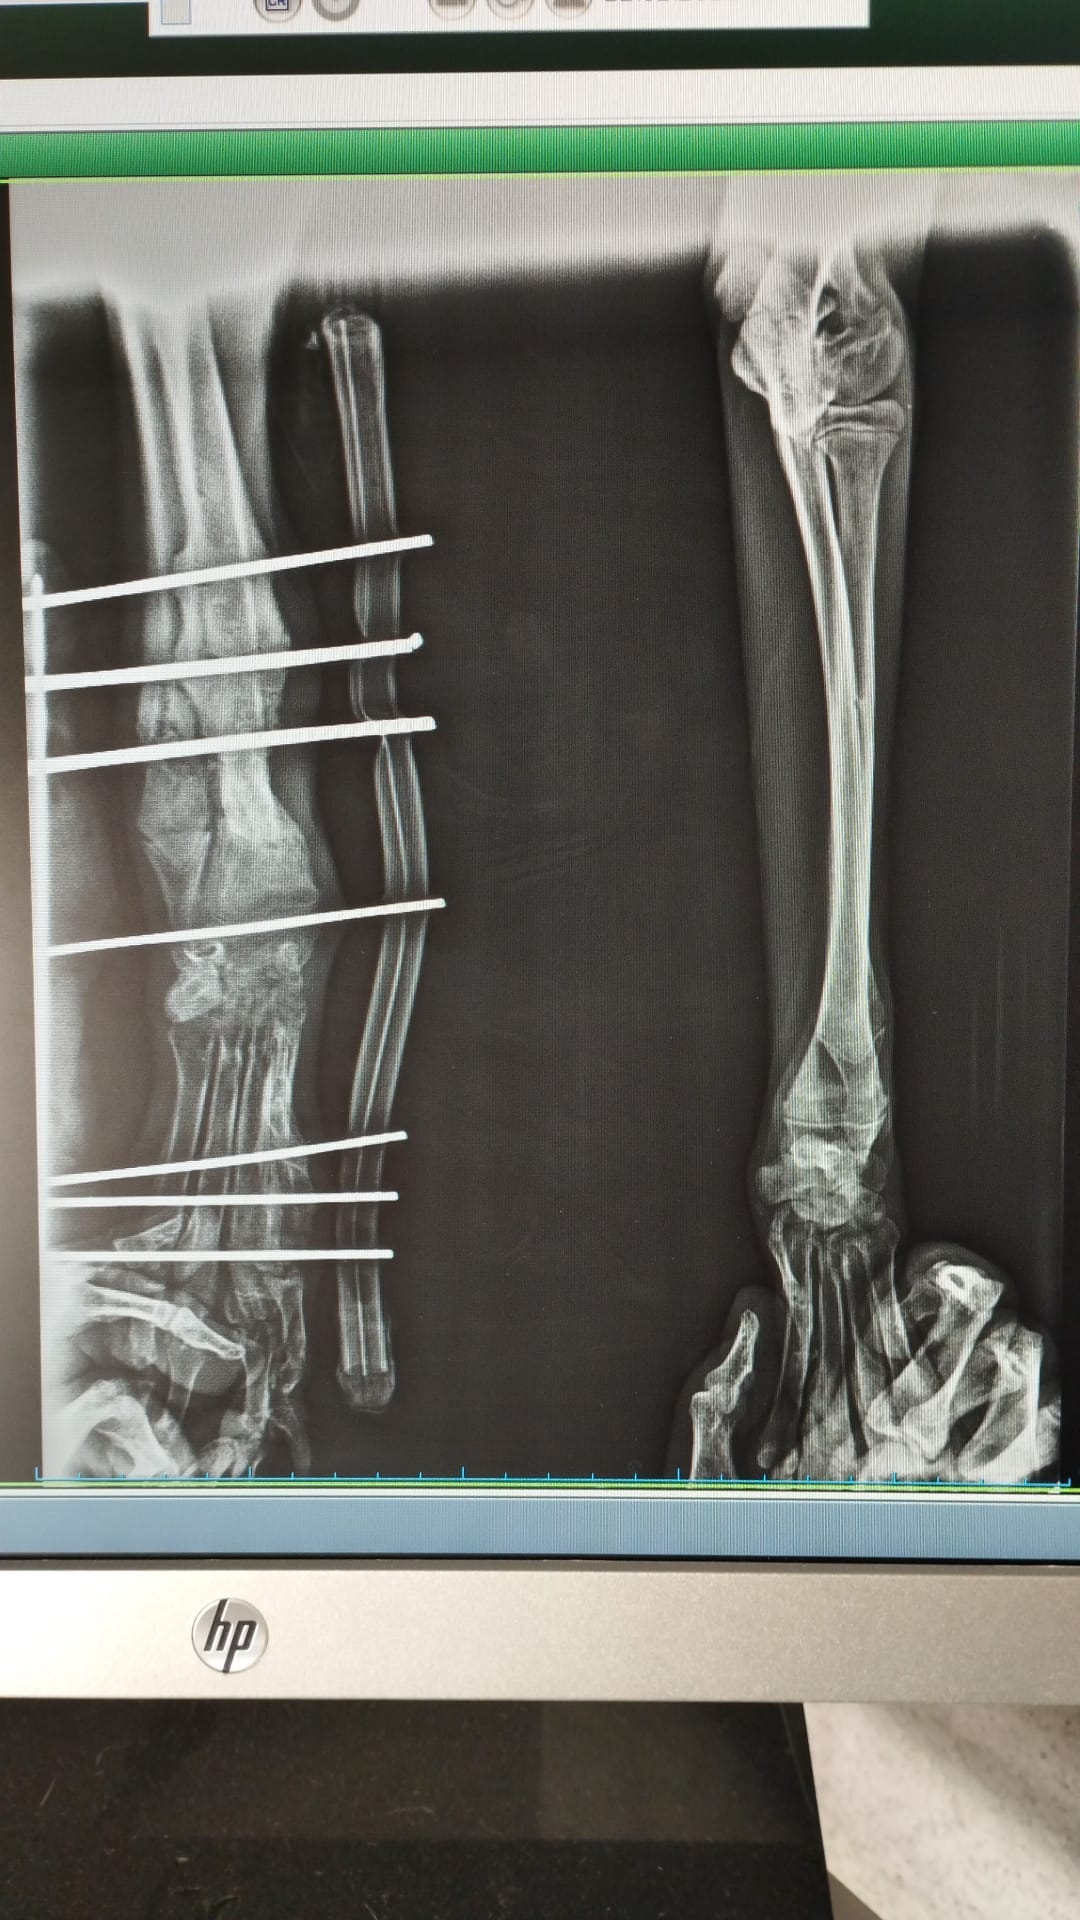

As you can see from the x-rays poor Patch had multiple breaks affecting three of his legs. He must have been in such a great amount of pain & so stressed.

He underwent several surgeries to repair the breaks with the use of plates & he also needed an external fixator.